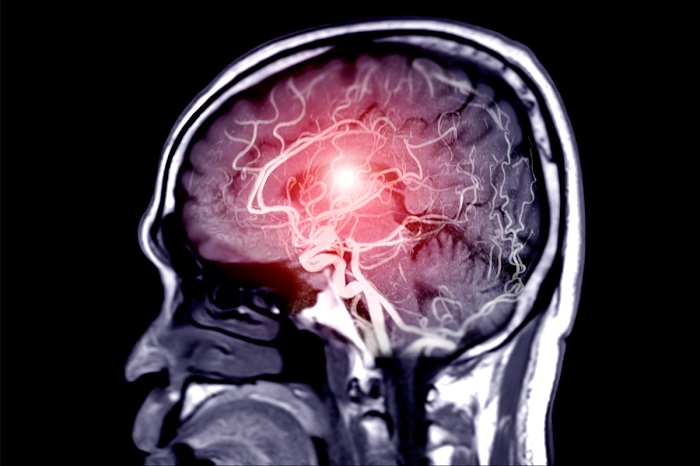

Што е мозочен удар?

Според Кливленд клиниката, мозочен удар е итна медицинска состојба која настанува кога мозокот не добива доволно крв. Затнат крвен сад или крварење во мозокот може да предизвика мозочен удар.